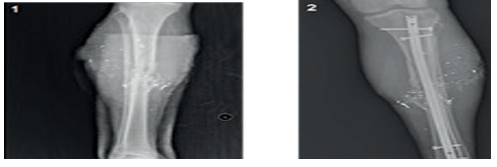

Patient with femoral fractures- Nonunion was observed in a total of 3 patients (6.25%). One of them had osteomyelitis. Union was achieved after pseudoarthrosis surgery in these patients. Delayed union occurred in six patients (12.5%). Union was achieved after dynamization in four patients. Delayed union was associated with deep infection in the other two patients, and union was achieved after infection treatment. Limb shortening was observed in three patients (2 patients with 2 cm, 1 patient with 1 cm) (Table 1). Representative preoperative and postoperative radiographs of tibial fractures treated with intramedullary nailing are presented in Figure 1.

Figure 1

Figure 1. (1); Tibial Fracture - Preoperative Radiograph (2); Postoperative Radiograph of Tibial Intramedullary Nailing